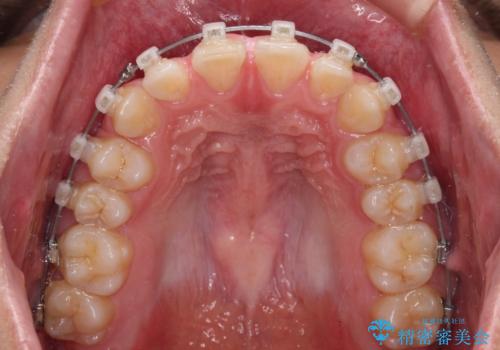

隙間とデコボコを治したい ワイヤー装置による矯正治療

- 矯正装置

- クリアブラケット

- 前歯のデコボコと隙間を気にして来院された患者様です。

治療手段としてはワイヤー装置でもインビザラインでも可能でしたが、インビザラインの自己管理は自信がないとのことで、ワイヤー矯正により隙間を閉じていくこととしました。

隙間の原因は舌の突出癖であったので、舌癖改善のためのトレーニングを指導しながら治療を進めて行くこととしました。

舌の突出癖がなかなか改善されず、治療開始時よりも隙間が大きく開いてしまう時期がありましたが、最終的にしっかりと閉じて終了することができました。